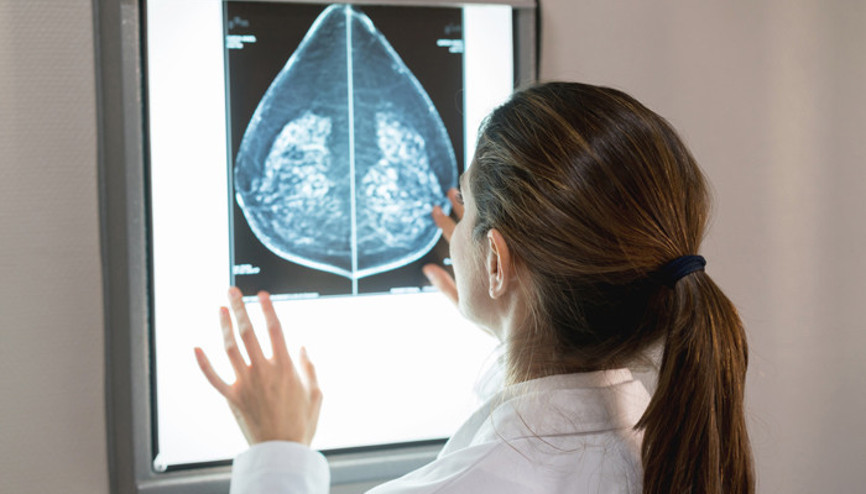

#Davina MccallSevil Gürkan rutin jinekolojik kontrollerinden birini yaptırıyordu. Aile geçmişi alınırken kurduğu bir cümleye takılan doktorunun istediği testlerde, kim bilir ne zamandır çok nadir bir kanserle yaşadığı ortaya çıktı. Elif Bozkurt Gültekin ise duş alırken kendi kendine yaptığı bir kontrol sırasında memesinde bir kitle olduğunu fark ettiğinde henüz 22 yaşındaydı. Muayeneler, testler derken 10 yıl süren bir tedavi bekliyordu Gültekin'i... Kanseri alt edenler, tanı aldıkları anları, sonrasında yaşadıklarını ve daha fazlasını Hurriyet.com.tr'ye anlattı...

#Çikolata KistiFlorida’da yeni bir hayata adım atarken içindeki ölümcül tehlikenin farkında bile değildi. “Harika görünüyorsun” diyen dostlarına gülümseyerek karşılık verirken, vücudu yavaş yavaş kanserle sarılıyordu. Louise Altese-Isidori’nin hikâyesi, sessizce ilerleyen bir hastalığın, yumurtalık kanserinin ne kadar sinsi olabileceğini çarpıcı biçimde gözler önüne seriyor.

#KayseriErken teşhis ve tedavi edildiğinde birçok kanserin hayatta kalma oranı oldukça yüksek. Ancak insanların belirtileri geç fark etmesi, görmezden gelmesi ya da sağlık kuruluşlarına başvurmakta geç kalması hem tedavinin zor ve acı verici olmasına hem de başarı ihtimalinin düşmesine yol açıyor. Peki kanserin belirtilerini nasıl tanıyacağız?